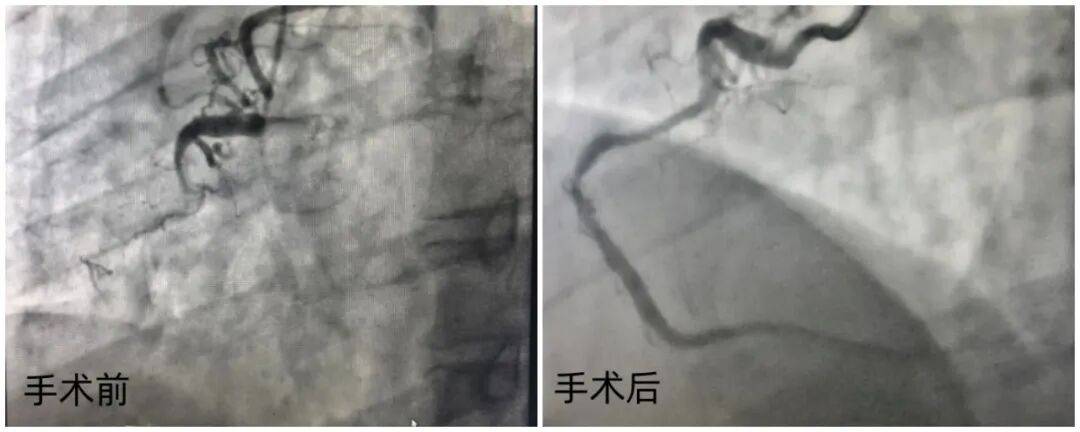

43岁的黄先生半年前开始频繁出现胸闷、胸痛症状,冠脉造影显示其前降支70-80%狭窄、回旋支远端次全闭塞,右侧冠状动脉近端更是完全闭塞,病情危急。

抵达阜外华中心血管病医院后,李牧蔚教授团队第一时间为黄先生完善了全面检查,而冠脉CTA结果显示,他的病情比预想中极为复杂:右冠状动脉近端和中远段存在两处长闭塞段,且整个血管走行极度迂曲、立体成角,给介入操作带来了极大挑战。

随后,她对狭窄病变部位进行小心翼翼的预处理,确保血管达到无明显狭窄、无中膜夹层的理想状态,再将药物球囊精准送达病变区域,让抗增殖药物均匀涂贴在斑块表面,从根源上抑制血管再狭窄。历经3个多小时的精细操作,手术顺利完成,黄先生的冠脉血管恢复通畅,自然构型与分支血流均得到完好保留。